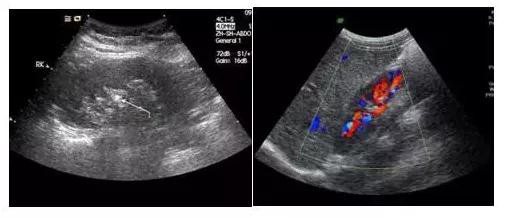

【更多】眾所周知,B超檢查是體驗中必不可少的項目,它可直觀而清晰地發現人體各臟器如肝、腎、胰腺、甲狀腺、乳腺、膀胱等的多種病變。B超又有黑白超和彩超之分,有時我們做黑白B超檢查,有時是彩色B超。其實對患者來說除了兩者價格有高低外,對它們之間的差別并不十分清楚。是越貴越…